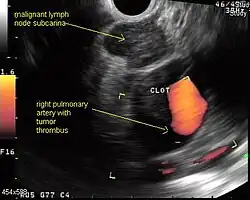

Endobronchial ultrasound (EBUS)

As mentioned in the table, EUS cannot reliably access right sided paratracheal lymph node stations 2R and 4R and may not be optimal for the left sided paratracheal lymph node stations either. An adaptation of the endoscopic ultrasound scope originally designed for the gastrointestinal tract is known as endobronchial ultrasound (EBUS). The instrument is inserted into the trachea rather than the esophagus. There are two types of EBUS bronchoscopes available: radial catheter probe and convex probe EBUS (CP-EBUS),[37] but only the latter concerns us here. Early experience with mediastinal staging by CP-EBUS appears very promising with sensitivities ranging from 92 to 96 percent in 4 series comprising 70 to 502 patients.[38][39][40][41]

Combined ultrasound

Many patients will, if given a choice, prefer an instrument which is inserted into the esophagus (EUS) over one which is inserted into the trachea (EBUS). Furthermore, many patients with suspected lung cancer will have other smoking related illnesses, such as emphysema or COPD, which makes a bronchoscopy-like procedure (EBUS) a higher risk than an upper endoscopy through the esophagus (EUS). An area of active and emerging research concerns the value of combining EUS and EBUS in a single session, one specialist following the other, or -even more convenient- a dual trained operator doing one or the other – or both- as needed.

EUS-FNA and EBUS-FNA are complementary techniques. EUS has the highest yield in the posterior inferior mediastinum, and EBUS is strongest for the superior anterior mediastinum. Some lymph node stations can only be accessed by one method and not the other (for example, station 2 and 4 L and 3 are hard or impossible to see by EUS, stations 5 and 8 cannot be biopsied by EBUS). Together, EBUS and EUS cover the entire mediastinum (except possibly station 6) and complete mediastinal staging should be possible with a combination of these two procedures. This combination could conceptually eliminate the need for most surgical mediastinoscopies and in fact be more comprehensive.

When combined, this approach has been termed "complete medical mediastinoscopy." EUS-FNA with EBUS may allow near-complete, minimally invasive mediastinal staging in patients with suspected lung cancer [42]